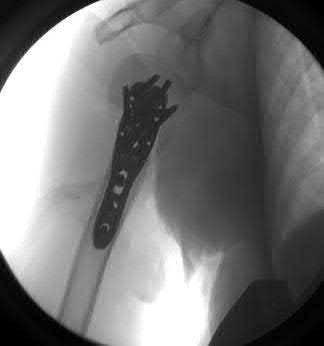

A 22-year-old rugby player has a history of recurrent anterior shoulder instability. A 3D reconstructed pre-operative CT scan is shown. The imaging demonstrates an inverted pear-shaped glenoid with a calculated anterior-inferior bone loss of 27%. What is the most appropriate surgical management to minimize his recurrence risk?

Options:

- Arthroscopic Bankart repair with capsular plication

- Arthroscopic remplissage alone

- Open inferior capsular shift

- Latarjet procedure (coracoid transfer)

- Thermal capsulorrhaphy

Correct Answer: Latarjet procedure (coracoid transfer)

Explanation:

In patients with anterior shoulder instability and significant glenoid bone loss (>20-25%, often creating an 'inverted pear' appearance), soft tissue procedures alone (like an arthroscopic Bankart repair) have unacceptably high recurrence rates. A bony augmentation procedure, most commonly the Latarjet procedure (transfer of the coracoid process with the attached conjoint tendon to the anterior glenoid neck), is the gold standard treatment.